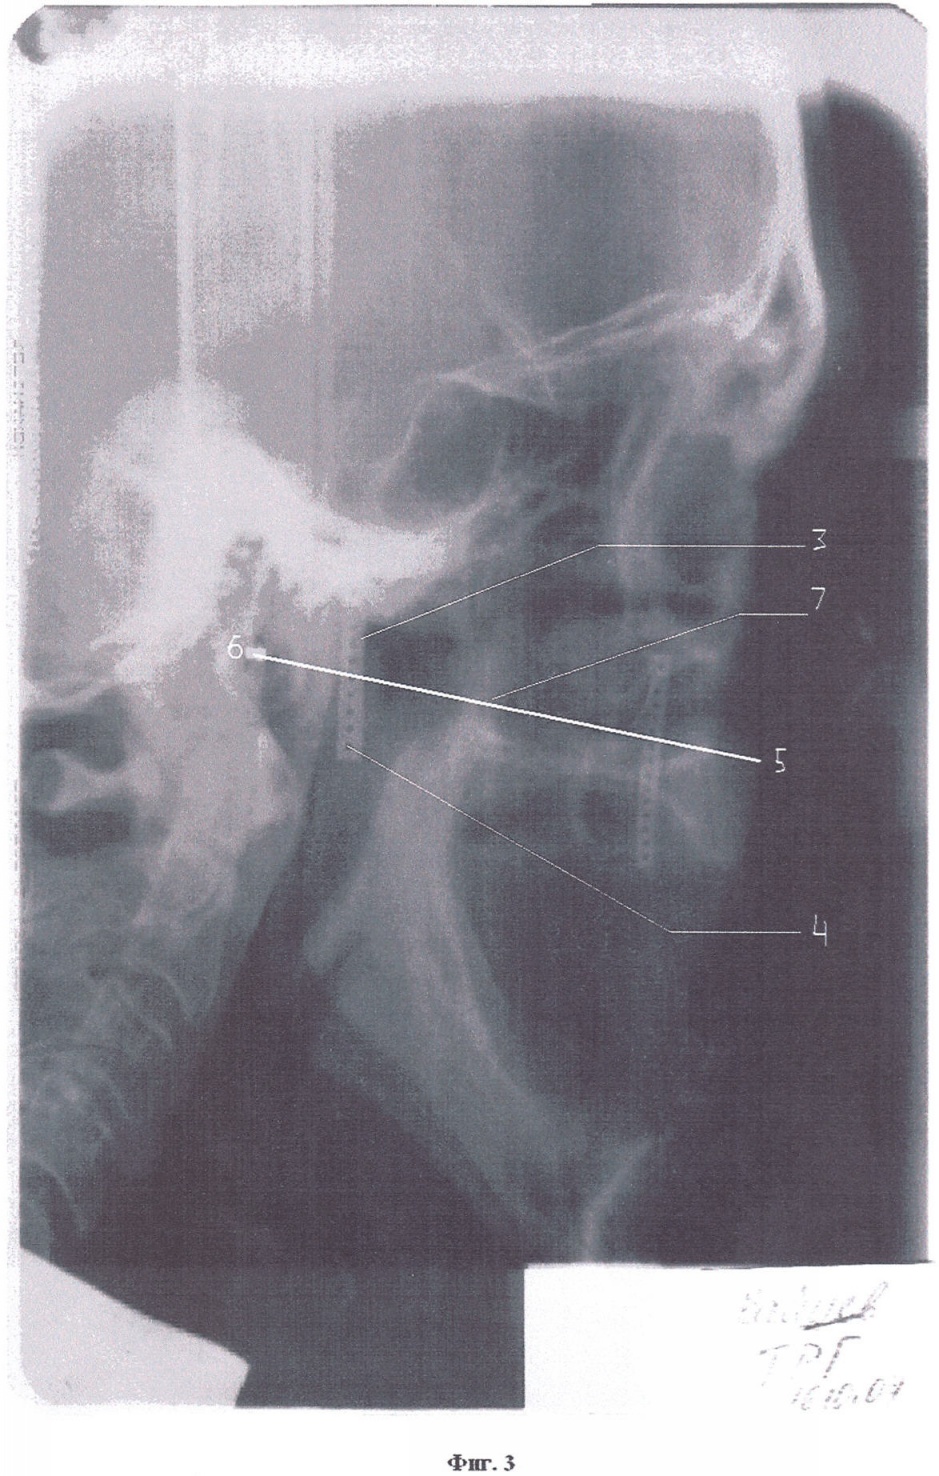

На лице пациента (Фиг.1 – схема) в области козелка уха 1 и крыла носа 2 в вертикальном направлении и параллельно друг другу закрепляют узкие самоклеящиеся рентгеноконтрастные ленты 3 с отверстиями 4 диаметром 1-3 мм (Фиг.2), например из пищевой алюминиевой фольги, свинцовой фольги. Для повышения точности прохождения носоушной линии на лице пациента отверстия на лентах небольшого диаметра и располагаются близко друг другу. Далее проводят боковую телерентгенографию головы. На телерентгенограмме (Фиг.3) через переднюю носовую ость 5 и основание наружного слухового прохода 6 проводят камперовскую горизонталь 7, которая пересекает изображения отверстий 4 на рентгеноконтрастных лентах 3. Определяют отверстия 4 на обеих лентах, через которые прошла камперовская горизонталь 7. С учетом расположения отверстий на первой и второй лентах проекция камперовской горизонтали легко переносится на лицо пациента (ленты на лице). Так получают индивидуальную носоушную линию, по которой строят протетическую плоскость на верхнем прикусном валике.